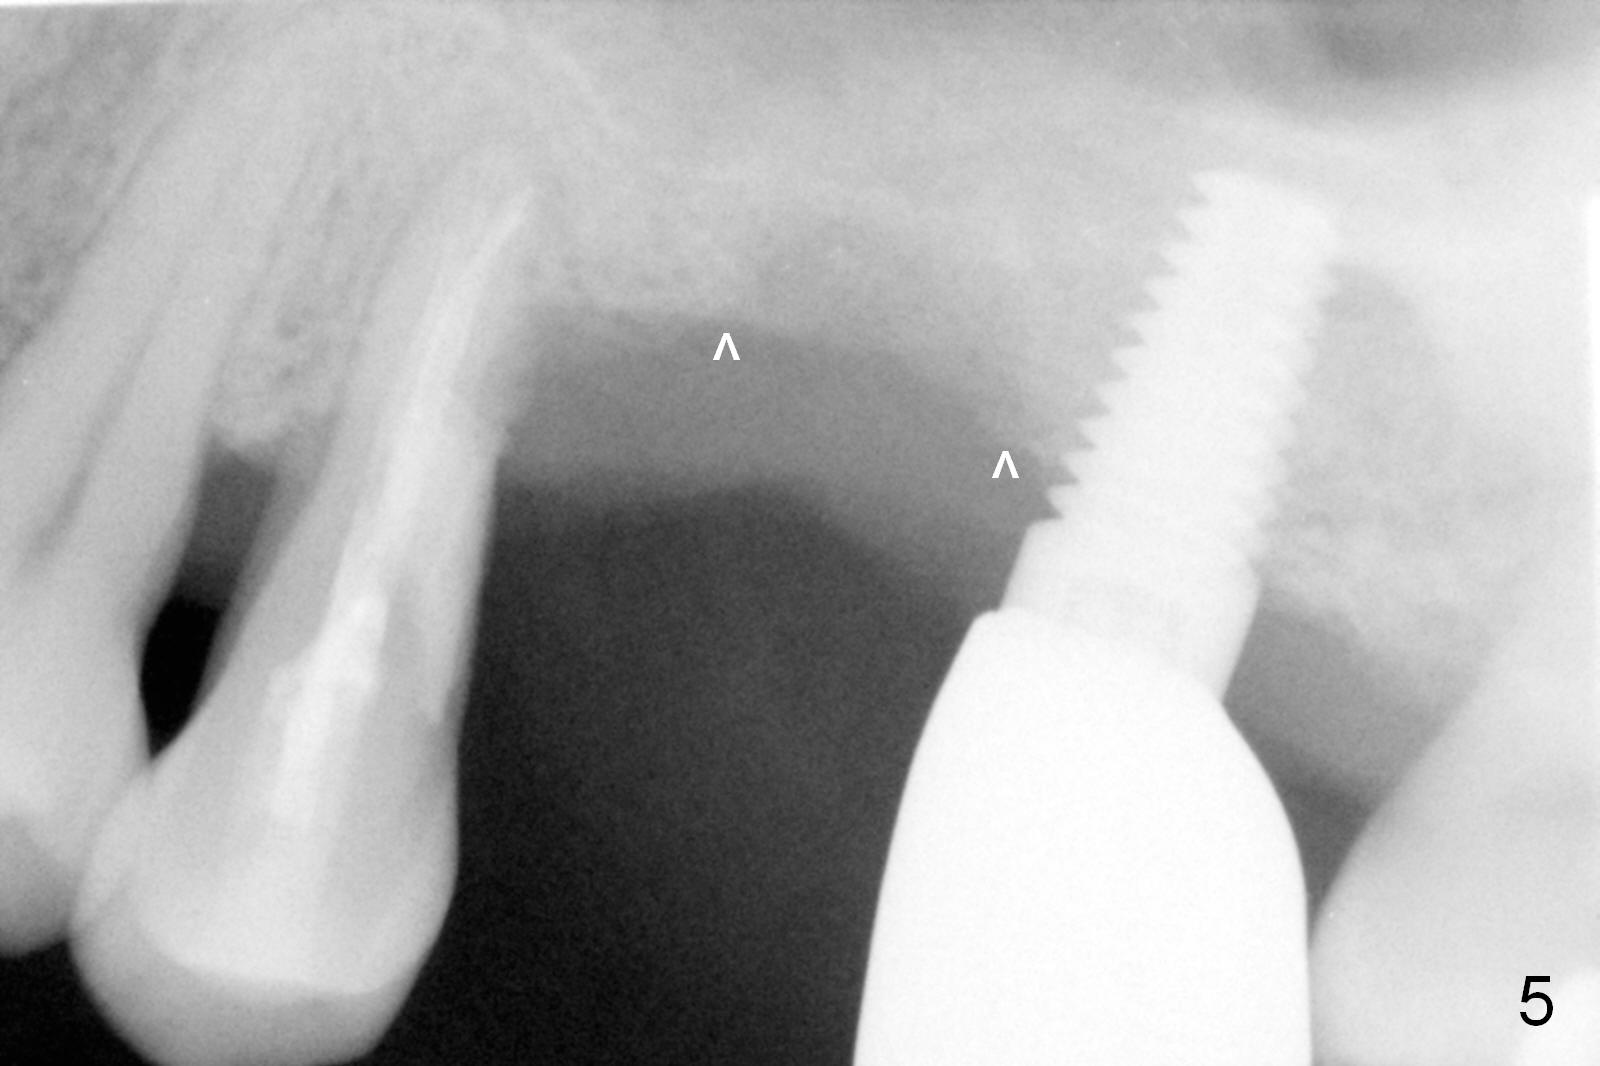

The implant site is healing a few days after loss (Fig.4 *) with a bony defect (Fig.5 ^). It appears that the implant at #14 was placed buccally. An incision is made palatally because of the presence of more keratinized gingiva (Fig.6). The buccal bone height is limited. The soft tissue in the bony defect is lifted into the sinus before bone graft (Fig.7 *).